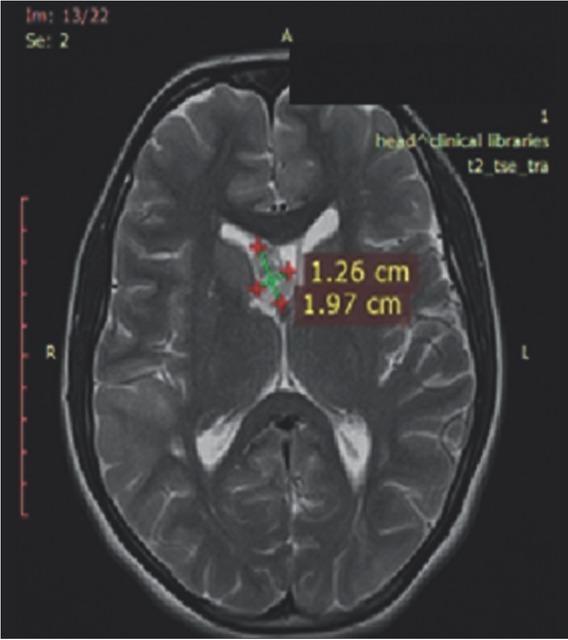

Figure 2